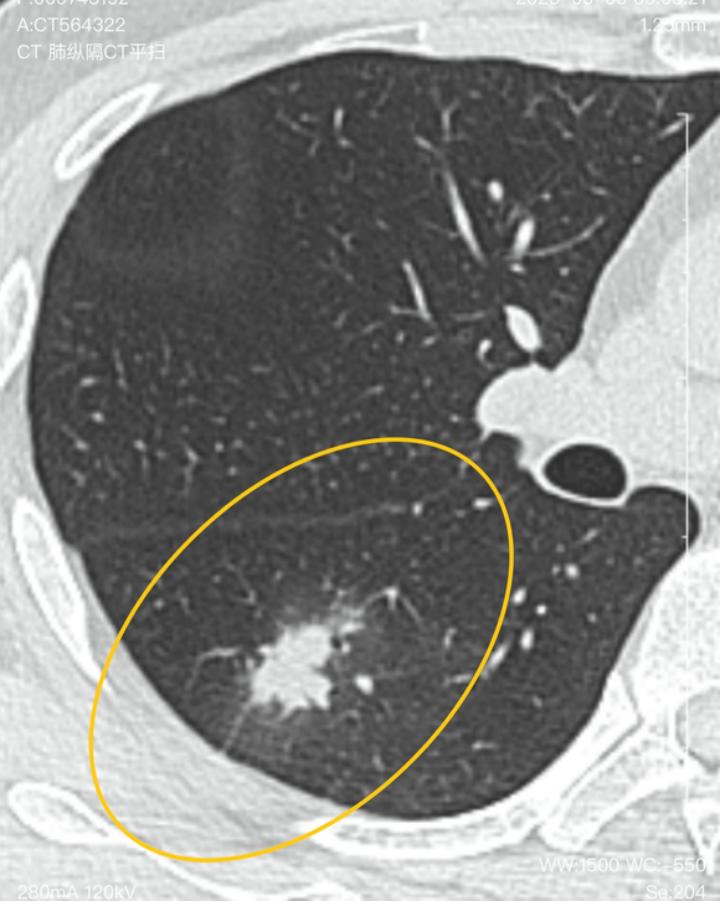

但是右肺下叶新发一个8mm的结节,还有多发斑片状磨玻璃密度灶。主任当时留言说考虑炎性,应该能消。吃莫西沙星12天又过了半个月复查,发现结节增大到2.4cm。医生说得住院检查。还建议穿刺!

看完片子,在这种情况下,可以断定是感染性病变。因为他结节的尺寸变化就符合感染性病变的特性。在抗炎处理的情况下,结节的尺寸从8mm增大到了24mm,体积翻了近20倍,直接排除肺癌和其他结节所致。那么首先考虑的是结核,其次考虑的是真菌感染(这可能也是抗炎处理无果的原因)。不过不用着急,现在肯定是良性的病变,后期可控,勿忧。